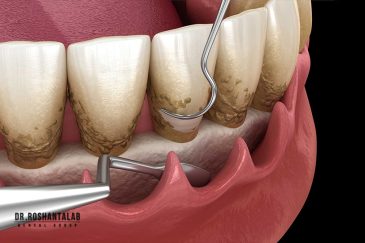

از عصب کشی و درمان ریشه دندان گرفته تا جراحی لثه و کشیدن دندان، تمامی مراحل توسط متخصص ترمیم دندان مدیریت میشود. ارائه باکیفیتترین خدمات ترمیم دندان برای سلامتی شماست.کاشت ایمپلنت فوری دندان